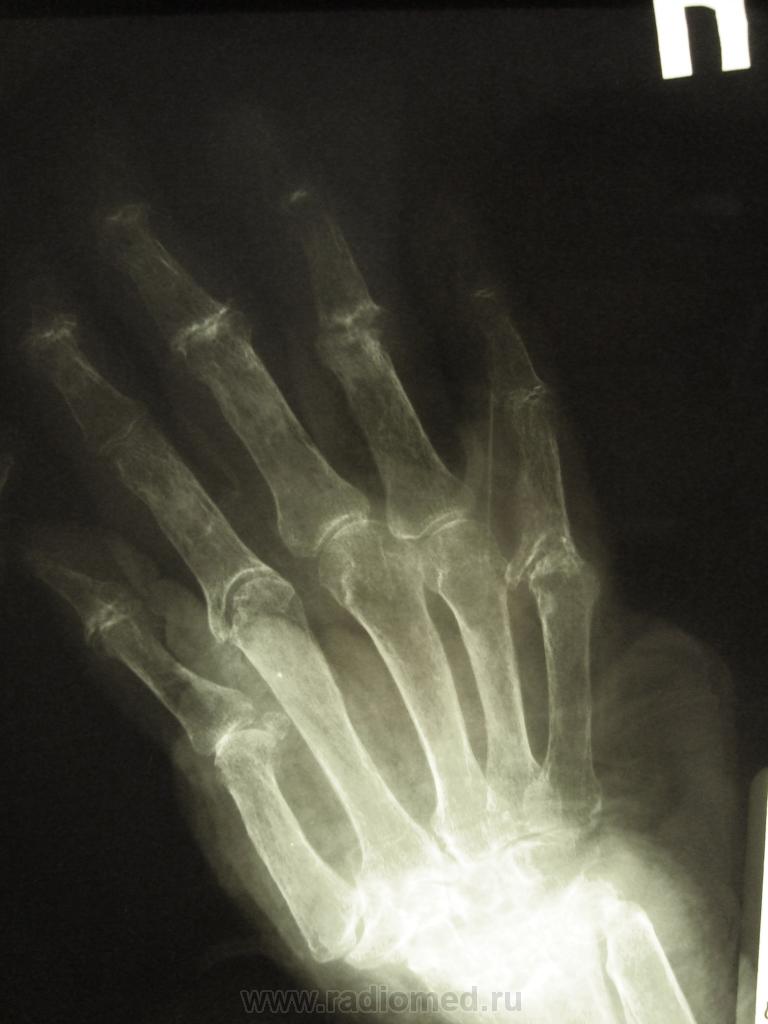

женщина,1930 г.р. , в наравлении -деформирующий артроз? В анализах повышено СОЭ, СРБ, ревмат. фактор.

Рентгенологически выделяют 4 стадии ревматоидного артрита: I стадия (начальная) — только околосуставной остеопороз; II стадия — остеопороз + сужение суставной щели; III стадия — остеопороз + сужение суставной щели + эрозии костей; IV стадия—сочетание признаков III стадии и анкилоза сустава. Раньше всего рентгенологические изменения при ревматоидном артрите появляются в суставах кистей и плюс-нефаланговых суставах.

после консультации ревматолога окружной больницы, пациентка приехала с диагнозом псориатический артрит. но продолжение этой истории следует, еще поедит на консультацию к другому специалисту, терапевт не согласен с диагнозом...

Ревматологи с областной больницы ставят DS: Ревматоидный  артрит, акт. II. R-стадия III. НФС III. Вторичный ДОА III ст. Анемия хронических заболеваний.

Без псориаза и его кожных проявлений - псориатическую артропатию диагностировать трудно...